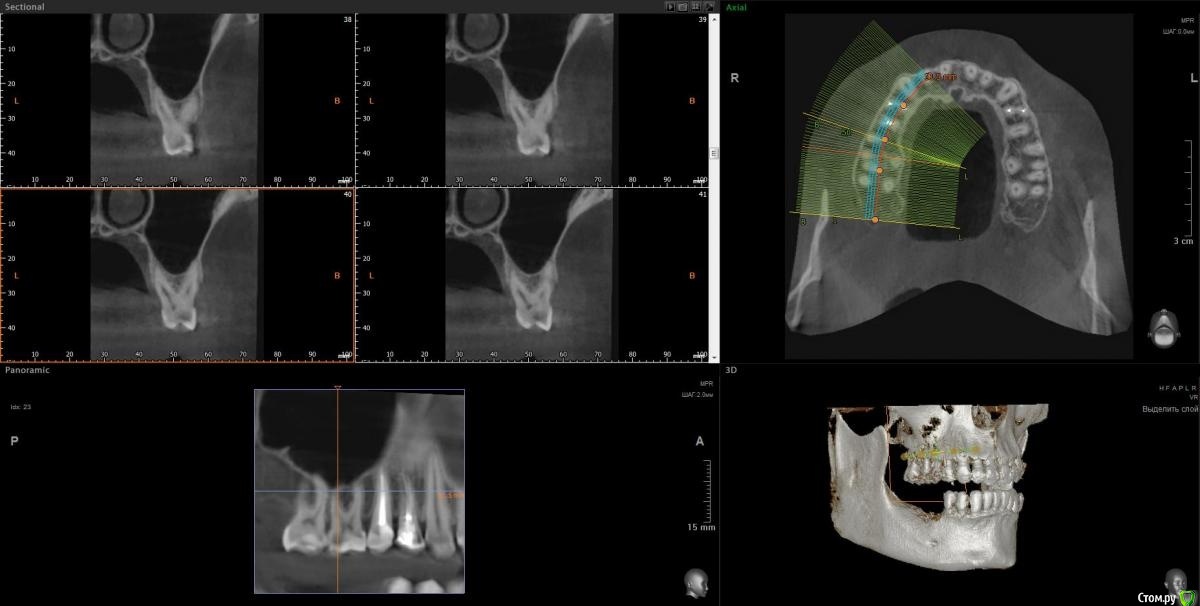

Vords Опубликовано 20 ноября, 2020 Поделиться Опубликовано 20 ноября, 2020 Доброго дня, форумчане. Прошу прощения за беспокойство. Хотел бы попытать счастье на форуме, поскольку все проведенные до этого консультации результатов не дали (( В общем ситуация такая: В начале сентября была неудачная попытка имплантации 46 и 47 зубов. 46 был удален и поставлены импланты nobel сразу в 46 и 47. В результате образовалась большая гематома и 2 недели были достаточно сильные боли в результате которых импланты были извлечены. После этого боль стала значительно более терпима и с ней я живу до сегодняшнего дня. И вроде уже через 20 дней нужно идти на вторую попытку имплантации, но боль еще не прошла. Никто (несколько терапевтов, имплантологов на КТ не видят причин для такой боли) - и идей ни у кого нет (( Было предположение, что отдает 45, так как очень сильно оголились корни после удаления 46 и его депульпировали, но боль не прошла. На данный момент идей совсем не осталось (кроме мифической идеи, что, возможно, 6 зуб сверху имеет пульпит (по теням на КТ) и отдает вниз. Я буду очень благодарен если у кого-то будут хоть какие-то идеи по этому вопросу, потому что жить с этой постоянной (пусть и не сильной) болью становится невозможно. Готов идти на очные консультации (но и было уже настолько много, что я, если честно, не уверен в их смысле). Ссылка на КТ https://yadi.sk/d/S3hKfHUWO-UTQg Сейчас пытаюсь разобраться как сделать качественные скрины нужных мест.Пока не выходит =(( Заранее благодарю. Ссылка на комментарий

wladdX Опубликовано 20 ноября, 2020 Поделиться Опубликовано 20 ноября, 2020 На н/челюсти ничего необычногоА вот вероятность пульпита зуба 16 довольно высокая 1 Ссылка на комментарий

Vords Опубликовано 20 ноября, 2020 Автор Поделиться Опубликовано 20 ноября, 2020 (изменено) На н/челюсти ничего необычногон_ч.jpgА вот вероятность пульпита зуба 16 довольно высокая16_1.jpg16_2.jpgБлагодарю, что нашли время ответить. А по Вашему опыту может ли так отдаваться вниз от 16? Или это "натянутая" версия? 16 не беспокоит от слова совсем Изменено 20 ноября, 2020 пользователем Vords Ссылка на комментарий

wladdX Опубликовано 21 ноября, 2020 Поделиться Опубликовано 21 ноября, 2020 Боли от зуба 16 "отдавать" в область зубов 46, 47 вполне себе могут. Это называется иррадиацией, в данном случае она происходит в системе тройничного нерва. 3 Ссылка на комментарий